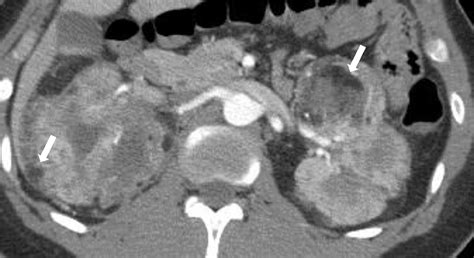

Renal Imaging and Surveillance

Renal involvement is a major contributor to morbidity in TSC, particularly in adults. The radiological surveillance of the kidneys is vital to prevent complications such as hemorrhage or renal failure. Imaging modalities of choice include ultrasound, CT scans, and MRIs.

The primary renal findings associated with Tuberous Sclerosis Radiology include:

• Angiomyolipomas (AMLs): These are the most common renal tumors in TSC. They are composed of blood vessels, smooth muscle, and fat. The presence of macroscopic fat is a diagnostic marker, which is best detected on MRI or CT scans using specific fat-suppression techniques.

• Renal Cysts: These can range from simple cysts to polycystic kidney disease, which, when occurring in TSC, often presents early in childhood and can lead to hypertension or decreased renal function.

• Renal Cell Carcinoma: While rare, the incidence is higher in TSC patients than in the general population, making it critical to distinguish between benign AMLs and potentially malignant masses.